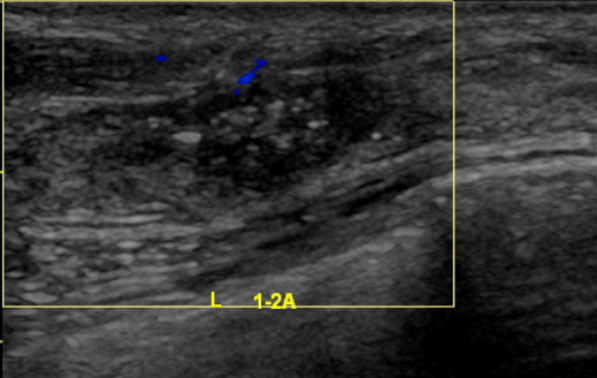

2021.6.9乳腺钼靶片提示:两侧乳腺呈不均匀致密型(ACRc),双乳腺体组织呈弥漫类结节改变。左乳外上象限见一分叶状肿块,边缘少许毛刺,大小约4.5cm×3.5cm,内见成簇细沙样钙化影,邻近皮下脂肪层见条索状密度增高、相应皮肤增厚,相应的乳后间隙部分显示欠清晰。右乳内未见明显异常密度结节或肿块形成,右乳内未见钙化灶。两侧腋下多发淋巴结显示(左腋下较多),双侧胸大肌未见异常,右乳皮肤、皮下、乳头、乳晕未见异常。

影像诊断:左乳外上象限占位(BI-RADS 5类),建议进一步检查;右侧乳腺增生(BI-RADS 1类);左侧腋下多发淋巴结显示。

图2.乳腺钼靶片(2021-6-9)